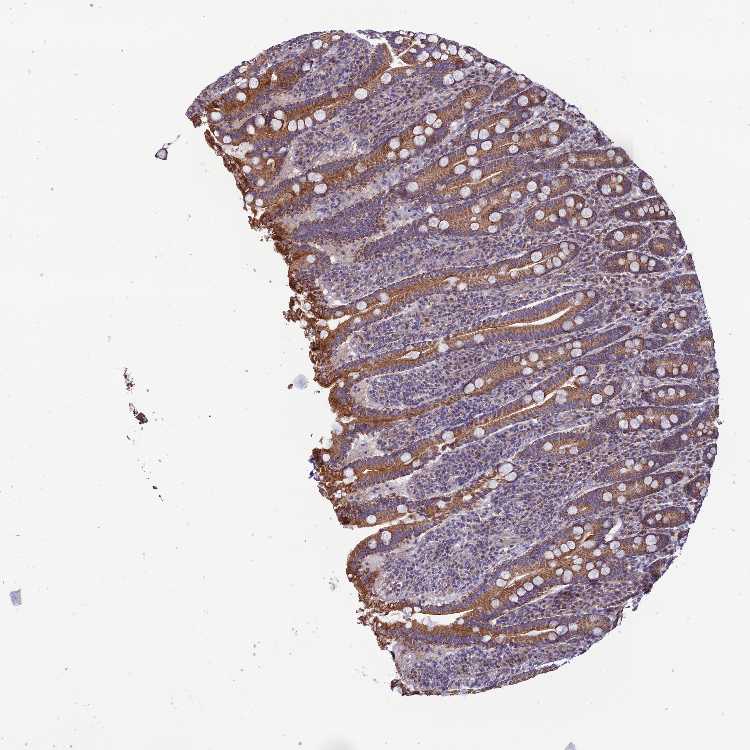

PADI3